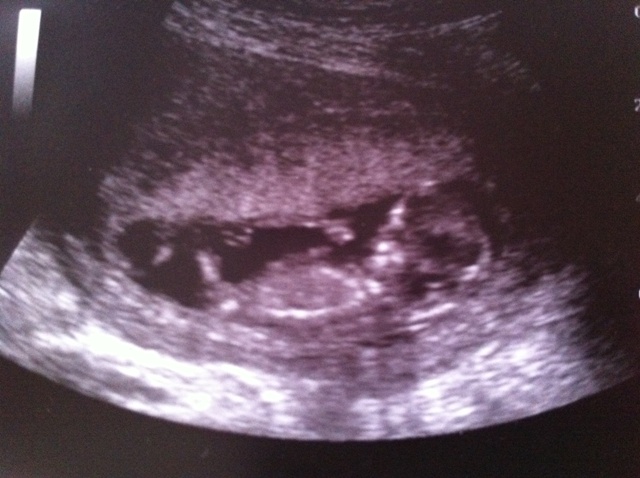

Take a look at these pics and tell me what you think. The profile shot is from 12w1d but I don't think you can see the nub (however I'm bad at this, so who knows). The potty shot is from 13w1d which I know is super early for a potty shot. However, the tech seemed to be very certain that it is a boy. What do you think? I'm just looking for guesses/opinions, I will find out next week either way but I want to see what you think. ;-) Thanks so much!!

Attachment 7960